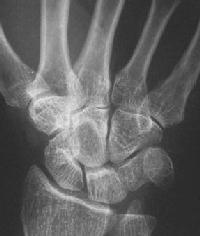

Plain films show dorsal impression of the capitate.